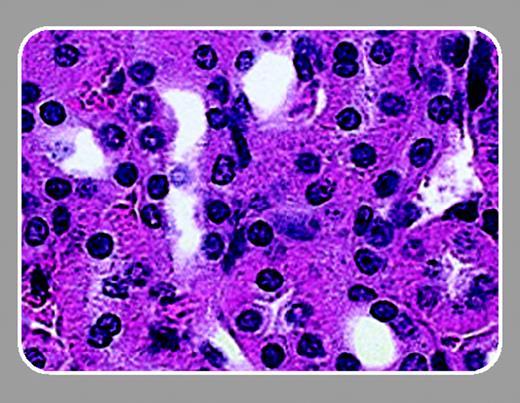

In this issue of Blood, Lavasseur and colleagues (page 4312) have followed up on the original description of successful correction of SCD in the mouse model. Similar to Pawliuk et al,5  Lavasseur et al demonstrate that lentivirus-mediated gene transfer of a modified human β-globin gene could inhibit the sickling of mouse SCD erythrocytes. In addition, they describe significant improvements in all clinical parameters measured, including liver and spleen necrosis and kidney function.

Lavasseur et al make 3 important points that should interest the readers of Blood. First, they have refined both the mouse model and the lentivirus vector. This group has developed an inbred SCD mouse model that allows transplantations to be done without the complications of graft-versus-host disease. In addition, Lavasseur et al used inbred SCD mice as both donors and recipients, ensuring that there were no normal mouse erythrocytes in the circulation. Thus, the improvements seen in the animals were the direct result of the globin transgene. Lavasseur et al also engineered the human β-globin gene to produce more potent antisickling activity and a greater affinity for α-globin.